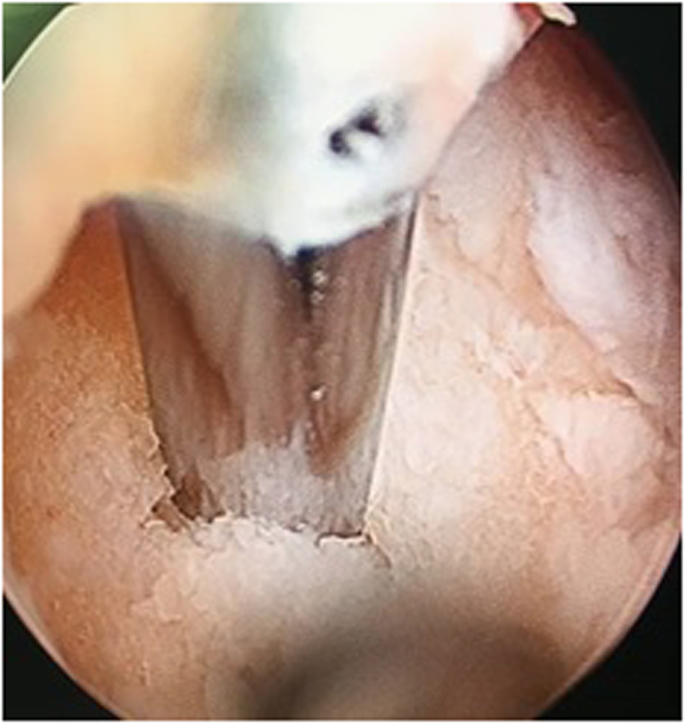

Arthroscopy was performed through standard anteromedial and anterolateral portal. A mid substance tear in ACL plus 1cm2 chondral lesion in medial femoral condyle were diagnosed (Fig. 2). The stump of the ACL was removed. Then, chondral abrasion and micro fracturing was performed to stimulate the regeneration of chondral lesion (Fig. 3). No meniscal lesion was detected.